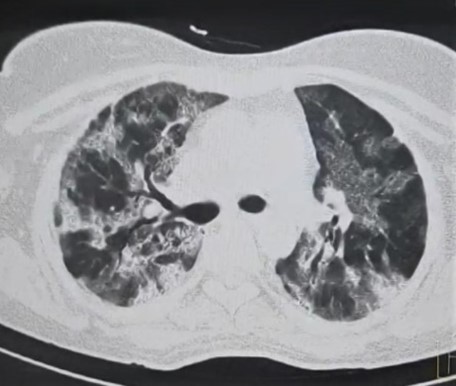

Initial HRCT